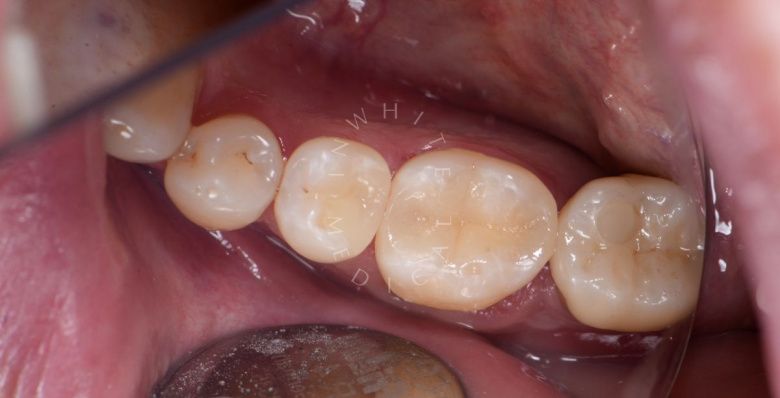

Художественная реставрация формы зубов

Стоматология Москва лучшие клиники. Художественная реставрация формы зубов - после процедуры

До После